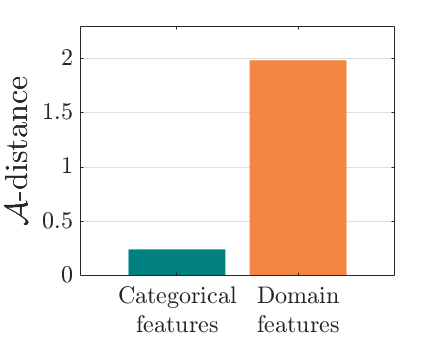

We adopt commonly-used statistical metrics, F1-score, recall and precision, to quantitatively evaluate classification performance. , and F1-score is the the harmonic mean of precision and recall. We report the average scores of these metrics for all examined methods. As suggested by [4], we utilize the -distance as a measure of domain divergence to quantitatively evaluate the separation of categorical and domain features. Similar to [19, 53], we train a SVM as a domain classifier to compute (the error of classifier) for the -distance, .

The classification performance of baselines and the proposed model are shown in Table. III. We observe that MIDNet outperforms the state-of-the-art on on the most important test data for average F1-score and recall. Among all the models in the ablation study, MIDNet+ achieves the best performance on and , demonstrating that metric learning contributes to the separation of seen categories in both domains. MIDNet outperforms MIDNet w/o , MIDNet w/o and MIDNet w/o on , illustrating the importance of all proposed components in MIDNet for the classification of unseen categories in the target domain. In addition, Fig. 7 (b) shows the effectiveness of mutual information disentanglement () to learn domain-invariant categorical features.